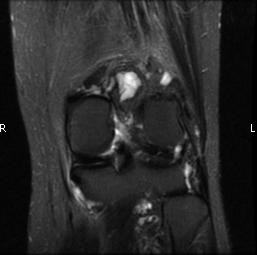

MRI (Fig. 1-10)

- Periarticular or synovial nodular mass with varying degrees of bone erosion.

- Nodular lesion with areas of hemosiderin (low signal on all sequences) and hemorrhage.

- On fat suppress images the tumor is high signal and hemosiderine cannot be seen.

- Joint effusions and bony erosions are well demonstrated. As with CT, contrast enhancement is typical.

Fig. 1-10: Magnetic Resonance of a PVNS of the knee shows a synovial mass with minimal bone erosion of the medial articular plate. On T1W and T2W images shows a tumor with low intensity areas (hemosiderin) and hemorrhage. Joint effusion is well demonstrated. Post contrast images demonstrate an irregular pattern of enhancement.